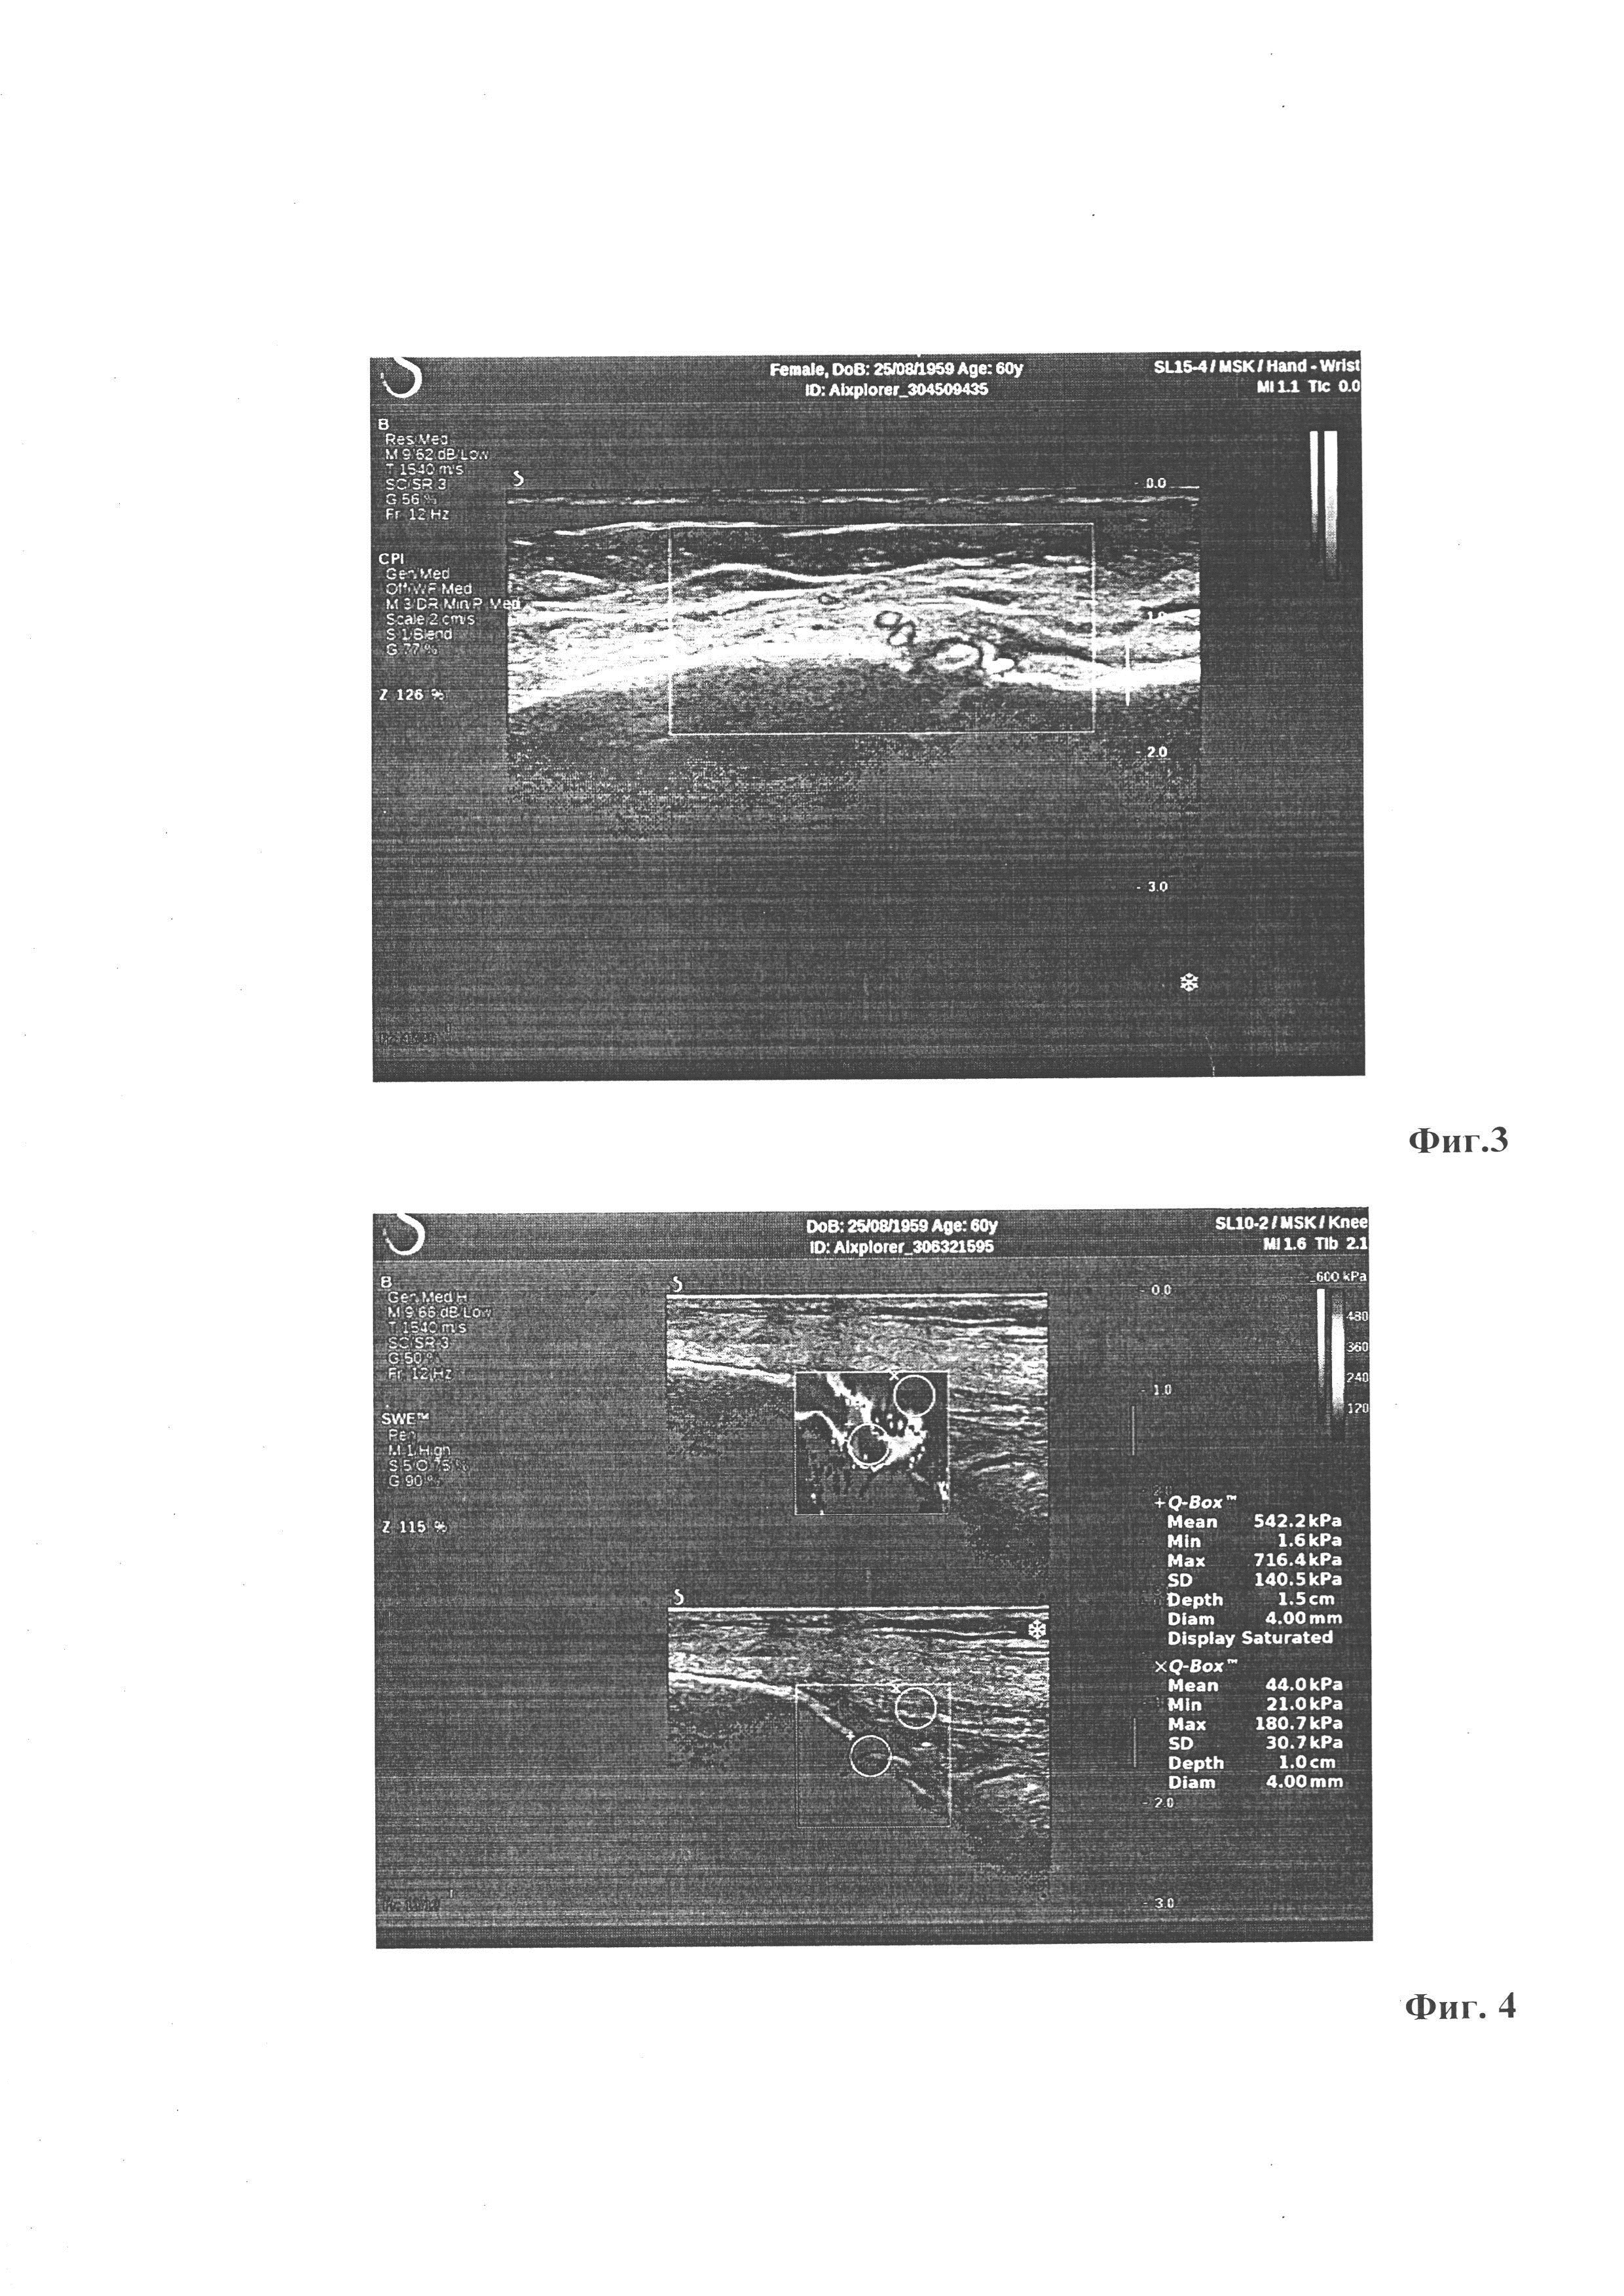

[24]

На Фиг. 4 - Эластограмма зоны перелома левой большеберцовой кости через 4 месяца в режиме УЭСВ. Жесткость костной мозоли 542,2 кПа (норма), жесткость мягких тканей 44 кПа (норма).

[36]

Повторное УЗИ зоны переломов пациентке Н. провели через 4 месяца после перелома по вышеописанной методике. Результаты этих исследований представлены на фиг. 3 - фиг. 4.

[37]

Заключение: жесткость костной мозоли левой большеберцовой кости через 4 месяца после перелома достигла 542,2 кПа, малоберцовой кости - до 403 кПа, что соответствует норме. Иммобилизацию можно снять.